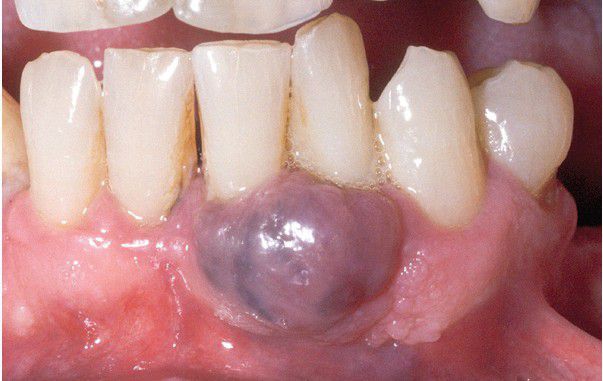

Peripheral Giant Cell Granuloma

. Nodular bluepurple mass of the mandibular gingiva.